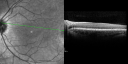

OCT SCAN: The OCT scans were normal. Photos confirm clinical findings.

FLUORESCEIN ANGIOGRAPHY: Fluorescein angiography shows early hyperfluorescence of tiny macular drusen scattered throughout the macula in both eyes.